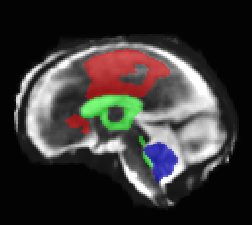

Limiting failures of machine learning systems is of paramount importance for safety-critical applications. In order to improve the robustness of machine learning systems, Distributionally Robust Optimization (DRO) has been proposed as a generalization of Empirical Risk Minimization (ERM). However, its use in deep learning has been severely restricted due to the relative inefficiency of the optimizers available for DRO in comparison to the wide-spread variants of Stochastic Gradient Descent (SGD) optimizers for ERM. We propose SGD with hardness weighted sampling, a principled and efficient optimization method for DRO in machine learning that is particularly suited in the context of deep learning. Similar to a hard example mining strategy in practice, the proposed algorithm is straightforward to implement and computationally as efficient as SGD-based optimizers used for deep learning, requiring minimal overhead computation. In contrast to typical ad hoc hard mining approaches, we prove the convergence of our DRO algorithm for over-parameterized deep learning networks with ReLU activation and a finite number of layers and parameters. Our experiments on fetal brain 3D MRI segmentation and brain tumor segmentation in MRI demonstrate the feasibility and the usefulness of our approach. Using our hardness weighted sampling for training a state-of-the-art deep learning pipeline leads to improved robustness to anatomical variabilities in automatic fetal brain 3D MRI segmentation using deep learning and to improved robustness to the image protocol variations in brain tumor segmentation. Our code is available at https://github.com/LucasFidon/HardnessWeightedSampler.